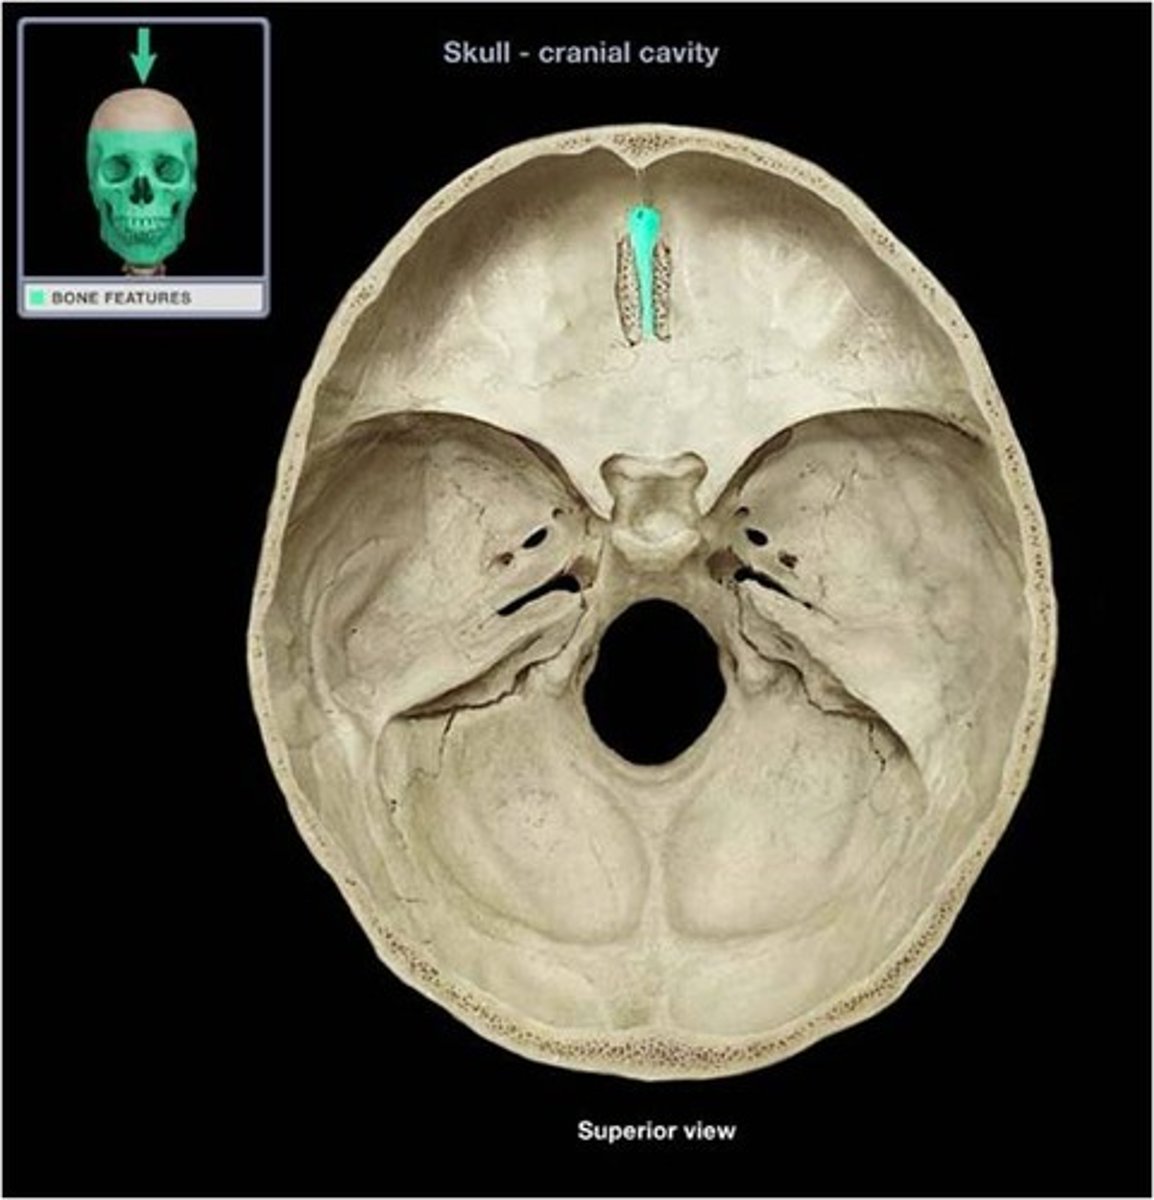

Crista galli

Vertical projection of the ethmoid bone.

Cribriform plate

Horizontal bone structure with olfactory foramina.